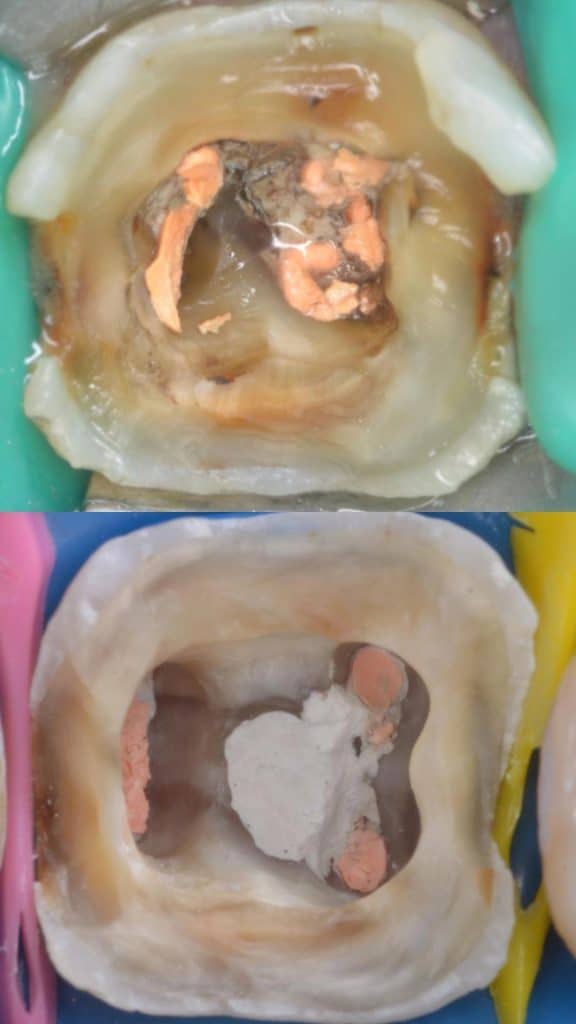

Removing old gutta percha showing perforation

Gutta percha removal

Obturation using cold lateral compaction technique with resin sealer and perforation repair using powder and liquid MTA